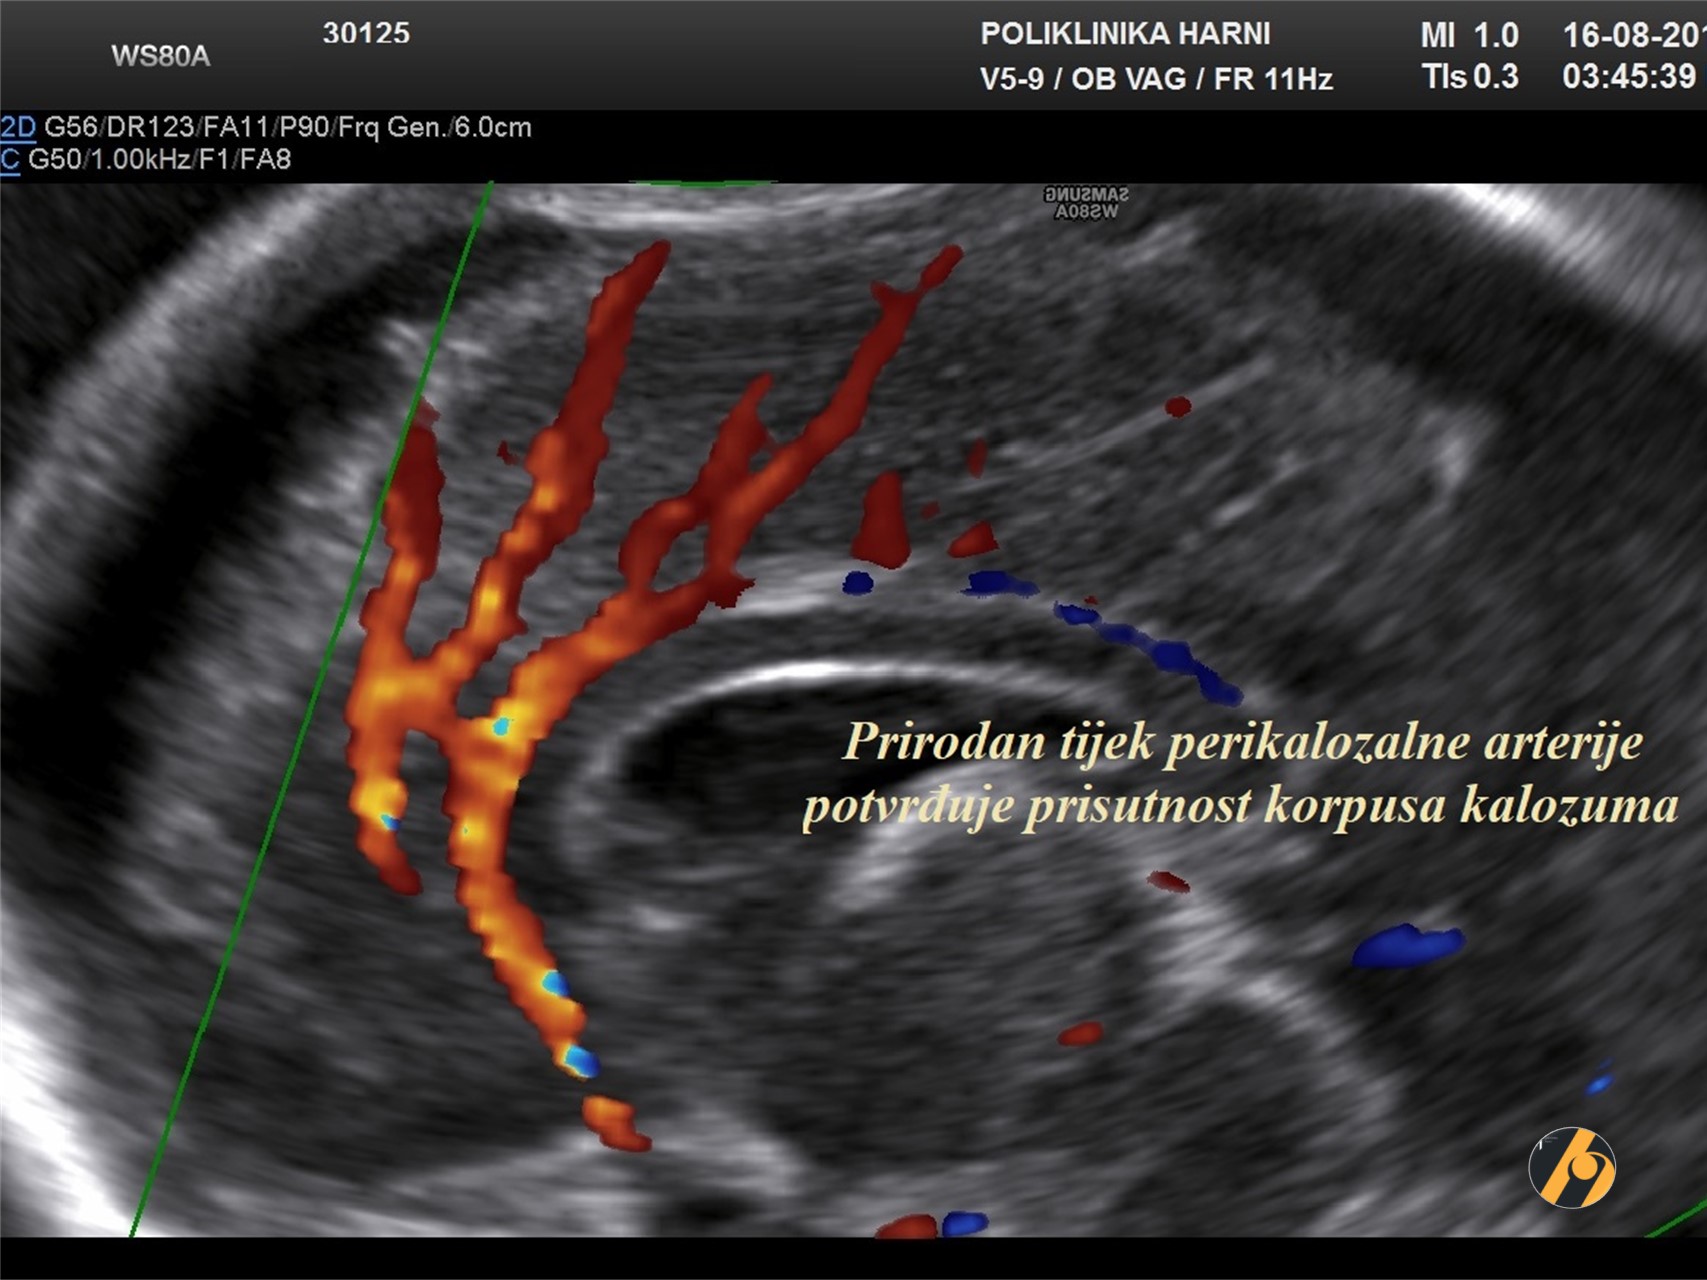

- Cavum septi pellucidi; u mediokoronalnom presjeku se prikazuje prekid kontinuiteta interhemisferične fisure korpusom kalozumom te cavum septi pelucidi ispod korpusa kalozuma, jasno odvojen od prednjih rogova lateralnih ventrikula.